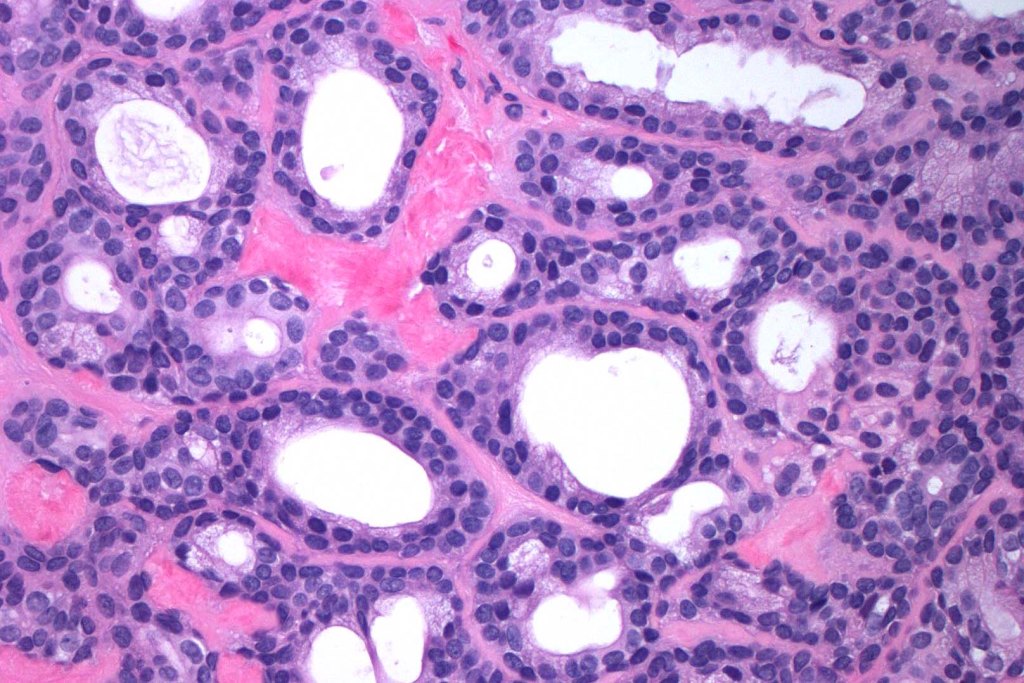

•Outer myoepithelial cells & inner layer of columnar cells with eosinophilic cytoplasm showing decapitation secretion

•DPAS +ve intracytoplasmic granules

•Adenomatous/papillary component (cystadenoma)